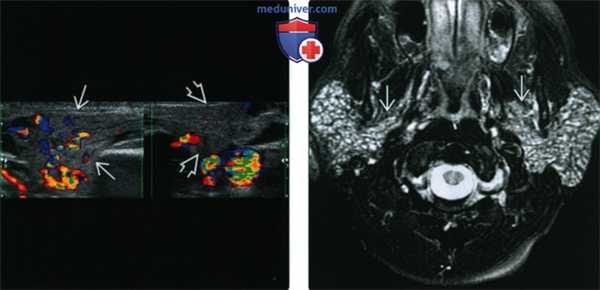

(Слева) Поперечное допплеровское УЗИ обеих околоушных желез у пациента с правосторонним паротитом. Правая железа увеличена в размерах, кровоток в ней усилен (по сравнению левой железой).

(Справа) MPT Т2ВИ FS, аксиальная проекция. Двустороннее увеличение околоушных желез, имеются многочисленные участки усиления сигнала. Пациент с обострением аутоиммунного сиалоаденита. Обратите внимание, что процесс диффузный и захватывает глубокие доли желез.

4. УЗИ при остром паротите:

• Увеличенная гипоэхогенная неоднородная железа

• Высокая чувствительность при диагностике камней

• Локальное скопление гипоэхогенного материала свидетельствует о формировании абсцесса

• Может использоваться для навигации при аспирации